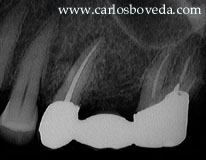

En esta oportunidad nos toca re-evaluar un segundo premolar superior izquierdo al que sometimos a tratamiento de conductos varios años atras por presentar una inflamación pulpar irreversible.

Clínicamente se aprecia un pequeño cambio de coloración en el margen gingival vestibular en relación a este diente. La zona se muestra liigeramente sensible a la palpación. Radiográficamente puede verse un área radiolúcida periradicular , ligeramente ovalada.

El sondaje del área evidencia una defecto vestobular amplio, confirmable radiograficamente con la sonda insertada.

Al igual que muchos de los participantes en el foro, sospechamos de la presencia de una fisura o un afractura vertical, por lo que programamos una cirugia exploratoria para analizar la situacion. El abordaje quirurgico nos mostro un amplio defecto periodontal en relacion a una fisura vertical unilateral, por lo que, luego de haber creado un pequeno surco en la extension de la fisura cin una punta ultrasonica procedimos a su sellado con el uso de geristore (Den-Mat). El procedimiento se complemento con tecnicas de RTG (Hueso natural - Bio-Oss + mebrana reabsorvible doble capa de colageno - Bio-Gide + injerto acelular).

La secuencia de imagenes muestra los detalles del procedimiento asi como los resultados clinicos a los 6 meses de ejecutada la intervencion.